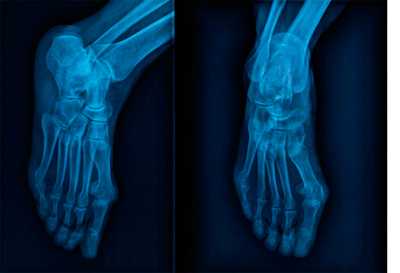

Для инструментальной диагностики используются рентгенограммы с\без нагрузки в сравнении со здоровой стороной, при их малой информативности рекомендовано выполнение стресс-рентгенограмм, аналогично приведёному выше тесту на нестабильность.

При рентгенографии все снимки выполняются в сравнении со здоровой стопой. Существует несколько основных рентгенологических признаков повреждения сустава Лисфранка. 1. Отсутствие параллельности медиального края основания 2-й плюсневой и медиального края медиальной клиновидной кости 2. Расширение между основаниями 1 и 2 плюсневых костей 3. Наличие костного фрагмента в области основания 2-1 плюсневой кости 4. Тыльный подвывих на боковой проекции 5. Разрыв линии предплюсне-плюсневого сочленения.

В сложных с диагностической точки зрения случаях целесообразно использование КТ и МРТ.